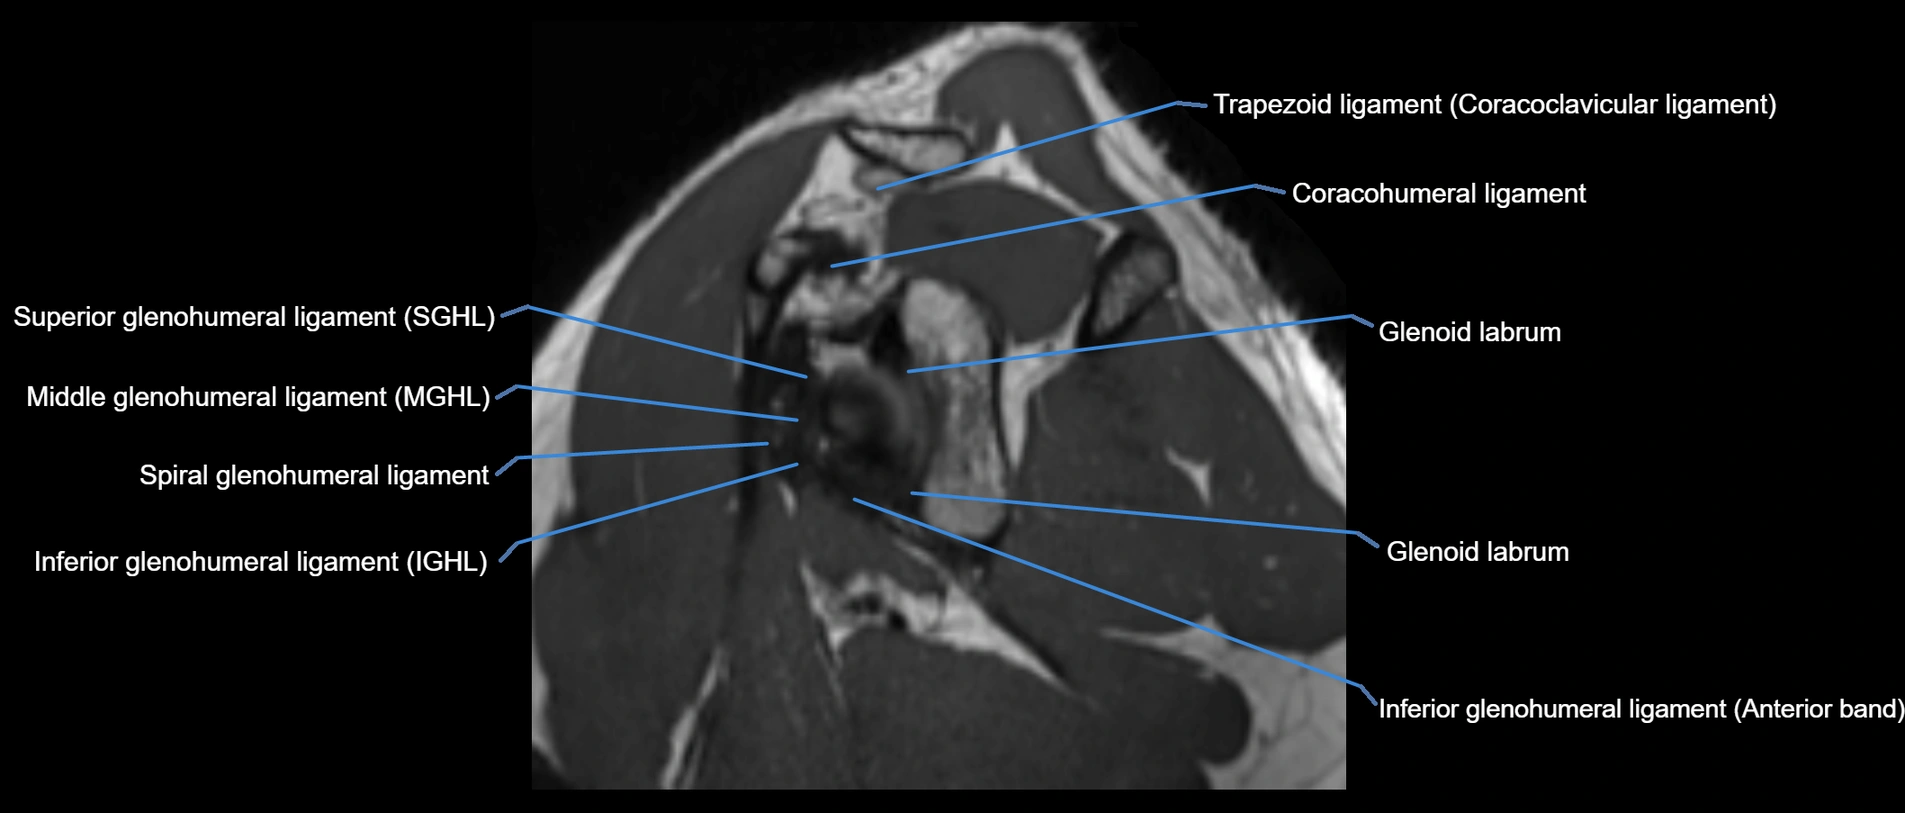

MRI images

image

MRI Appearance

• T1-weighted images:

• Normal ligament: Low signal (dark linear band) spanning acromion to clavicle.

• Surrounding fat planes: Bright, delineating the ligament clearly.

• Marrow of clavicle and acromion: Bright due to fatty content.

• Tears: Discontinuity or irregular thickening with intermediate-to-bright signal.

• Chronic injury: Thinning, fraying, or irregular low-signal fibers with adjacent scarring.

• T2-weighted images:

• Normal ligament: Low signal, homogeneous.

• Partial tear or sprain: Focal hyperintensity or thickening.

• Complete tear: Discontinuity with fluid-bright gap between clavicle and acromion.

• Associated edema: Bright signal in distal clavicle or acromion marrow.

• STIR:

• Normal ligament: Dark linear band.

• Injury or inflammation: Bright hyperintense signal in and around ligament fibers.

• Highlights periligamentous soft-tissue edema, especially in acute trauma.

• Proton Density Fat-Saturated (PD FS):

• Normal ligament: Low signal, uniform thickness.

• Partial tear or sprain: Bright signal or contour irregularity.

• Complete tear: Clear discontinuity with bright signal gap and joint effusion.

• Excellent for assessing joint capsule, coracoclavicular ligaments, and periarticular edema.